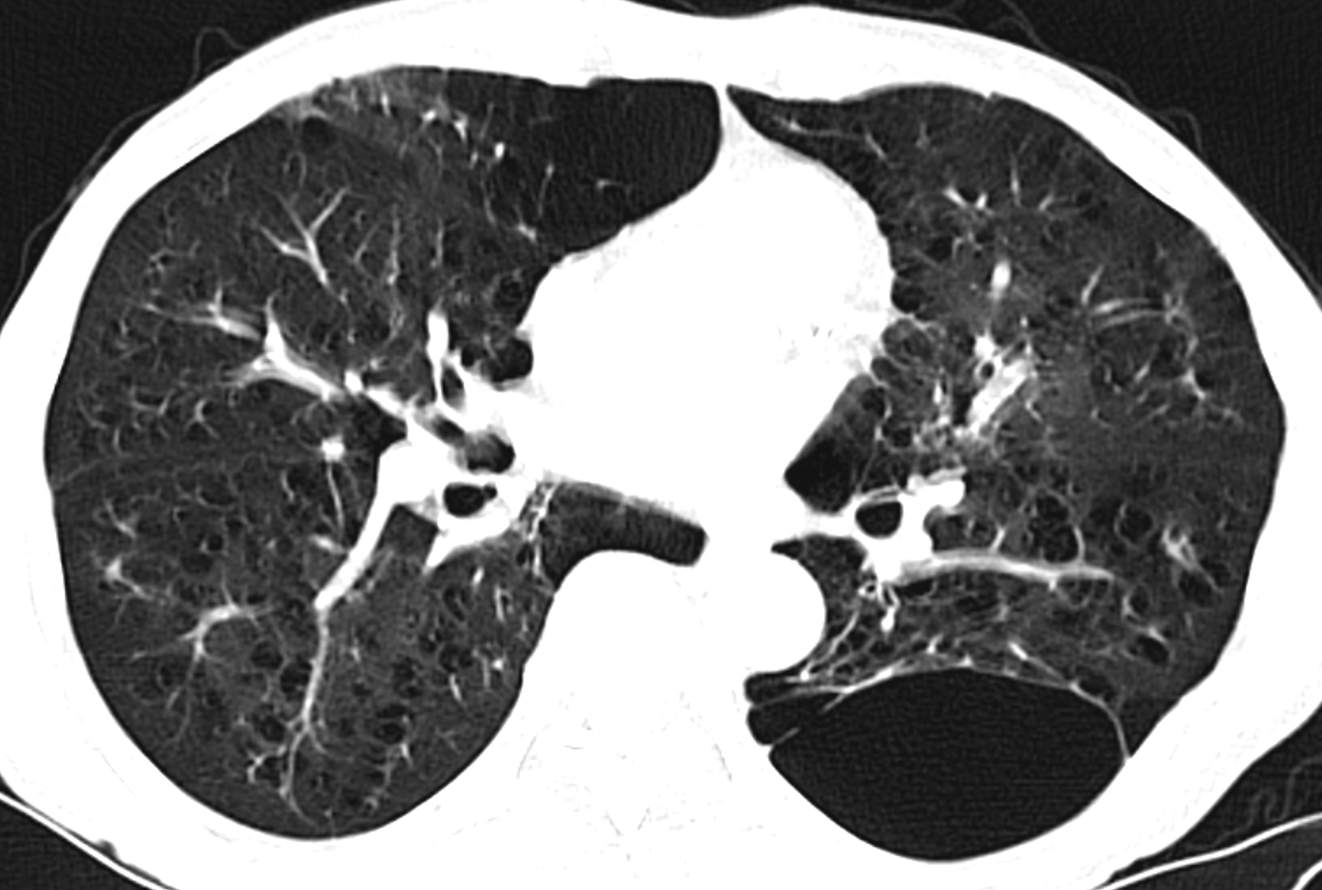

因CT明显异常而复诊。

因患者有肺大泡,肺功能存在一定禁忌。